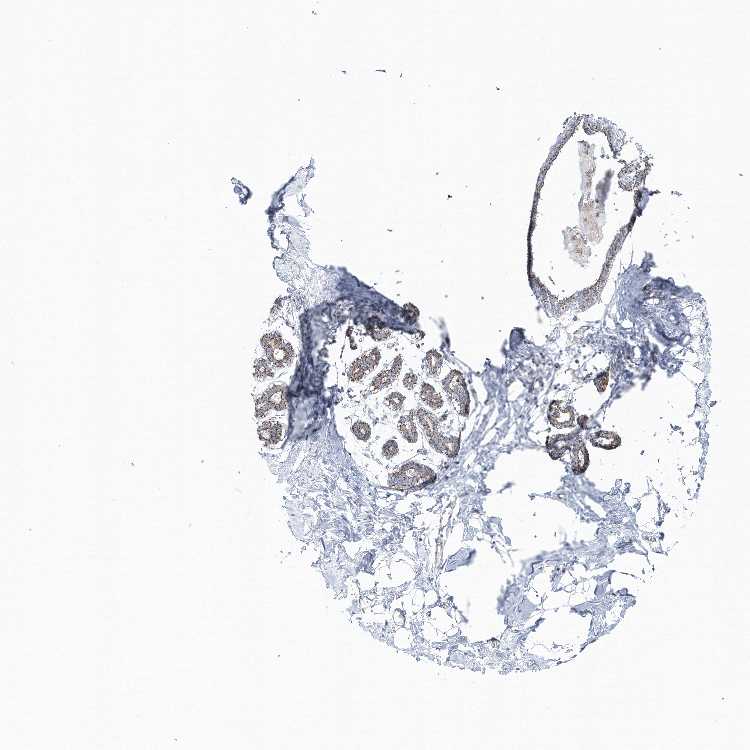

BREAST - Antibody stainingi

Antibody staining in the annotated cell types in the current human tissue is reported as not detected, low, medium, or high, based on conventional immunohistochemistry profiling in selected tissues. This score is based on the combination of the staining intensity and fraction of stained cells.

Each image is clickable and will lead to virtual microscopy that enables deeper exploration of all samples and also displays staining intensity scores, fraction scores and subcellular localization as well as patient and tissue information for each sample.

Antibody HPA037473Antibody HPA037474

Adipocytes Not detectedLow

Glandular cells LowMedium

Myoepithelial cells Not detectedNot detected